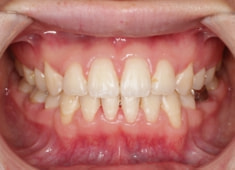

治療前

治療後(2年9ヶ月後)